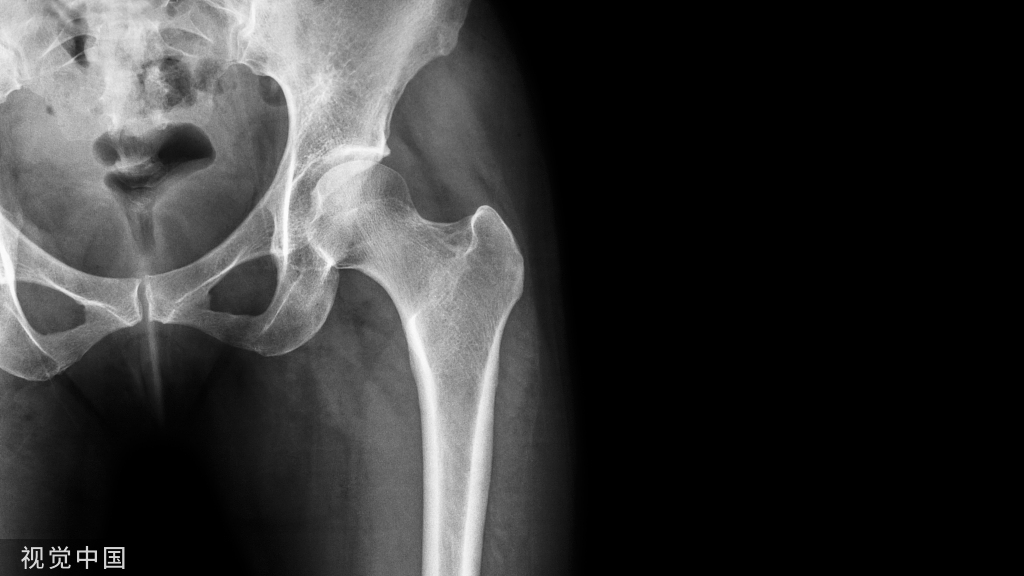

特殊类型踝关节骨折虽然临床少见,但是其诊断、治疗不准确会带来诸多不良后遗症,以致踝关节功能障碍,今天我们就来学习一下Maisonneuve 骨折!